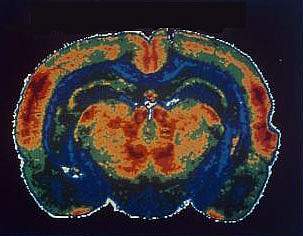

IDr. Arthur Brody of the David Geffen School of Medicine at UCLA and his colleagues used positron emission tomography (PET) to scan the brains of 11 smokers and assess nicotine's activity. They used a recently-developed radiotracer that binds nicotine receptors but can be displaced when nicotine comes in to bind the receptors instead. During scanning, the participants smoked different amounts. Their craving was measured with the Urge to Smoke scale, which assesses responses to 10 craving-related questions.

In the August 2006 issue of the Archives of General Psychiatry, the researchers report that the amount of nicotine in just one puff of a cigarette occupied about 30% of the brain's most common type of nicotine receptors, while three puffs of a cigarette occupied about 70%. Smoking a whole cigarette filled more than 88% of the receptors and alleviated craving to some extent. Only when nearly all of the receptors were occupied, however, after smoking at least 2 and a half cigarettes, did the smokers becomes satiated, or satisfied, for a time. Soon, however, this level of satiation wore off, driving the smoker to continue smoking throughout the day to satisfy their cigarette cravings.